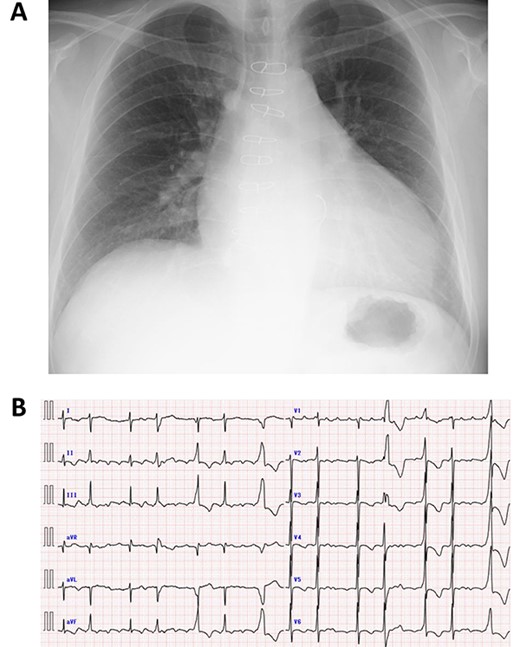

A 50-year-old male who had undergone MV repair 14 years ago due to traumatic mitral valve regurgitation was presented to our department due to heart failure with New York Heart Association (NYHA) III classification. Chest X-ray showed moderate cardiomegaly, and electrocardiogram showed atrial fibrillation with controlled heart rate (Fig. 1A and B). Transthoracic echocardiogram showed moderate MR with severely impaired bi-ventricular function; left ventricular ejection fraction of 20%, (Fig. 2A and B). Coronary angiography showed no significant stenosis. Although indication for mitral valve surgery was marginal [2], surgical intervention was decided to prevent further deterioration of bi-ventricular function.